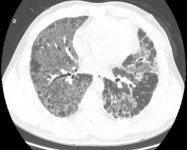

图:(从左至右)急性、亚急性、慢性

1、所谓急性HP,就是患者接触了较高水平的暴露,例如有患者喜欢饲养鸟类,尤其喜欢宠物鸽子,于是到交易市场去看,在这个过程中,可能出现了间断高水平暴露,于是一些易感个体就在很短的时间内(4到12小时)出现了流感样症状和呼吸道症状,而肺内则出现了一些磨玻璃影。

2、也有一些患者急性发作伴发热,劳力性呼吸困难、乏力和咳嗽,影像表现为小叶中央性的弥漫性的腺泡结节,称之为亚急性HP

3、还有些患者持续性低水平暴露,起病很隐匿,当我们发现时,已经出现了劳力性呼吸困难,干咳,体重减轻和乏力,而影像出现了既有磨玻璃影,也有肺纤维化的表现,称之为慢性HP